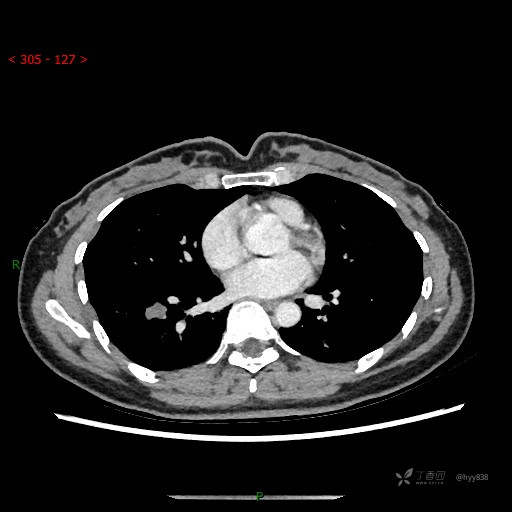

增强动脉期